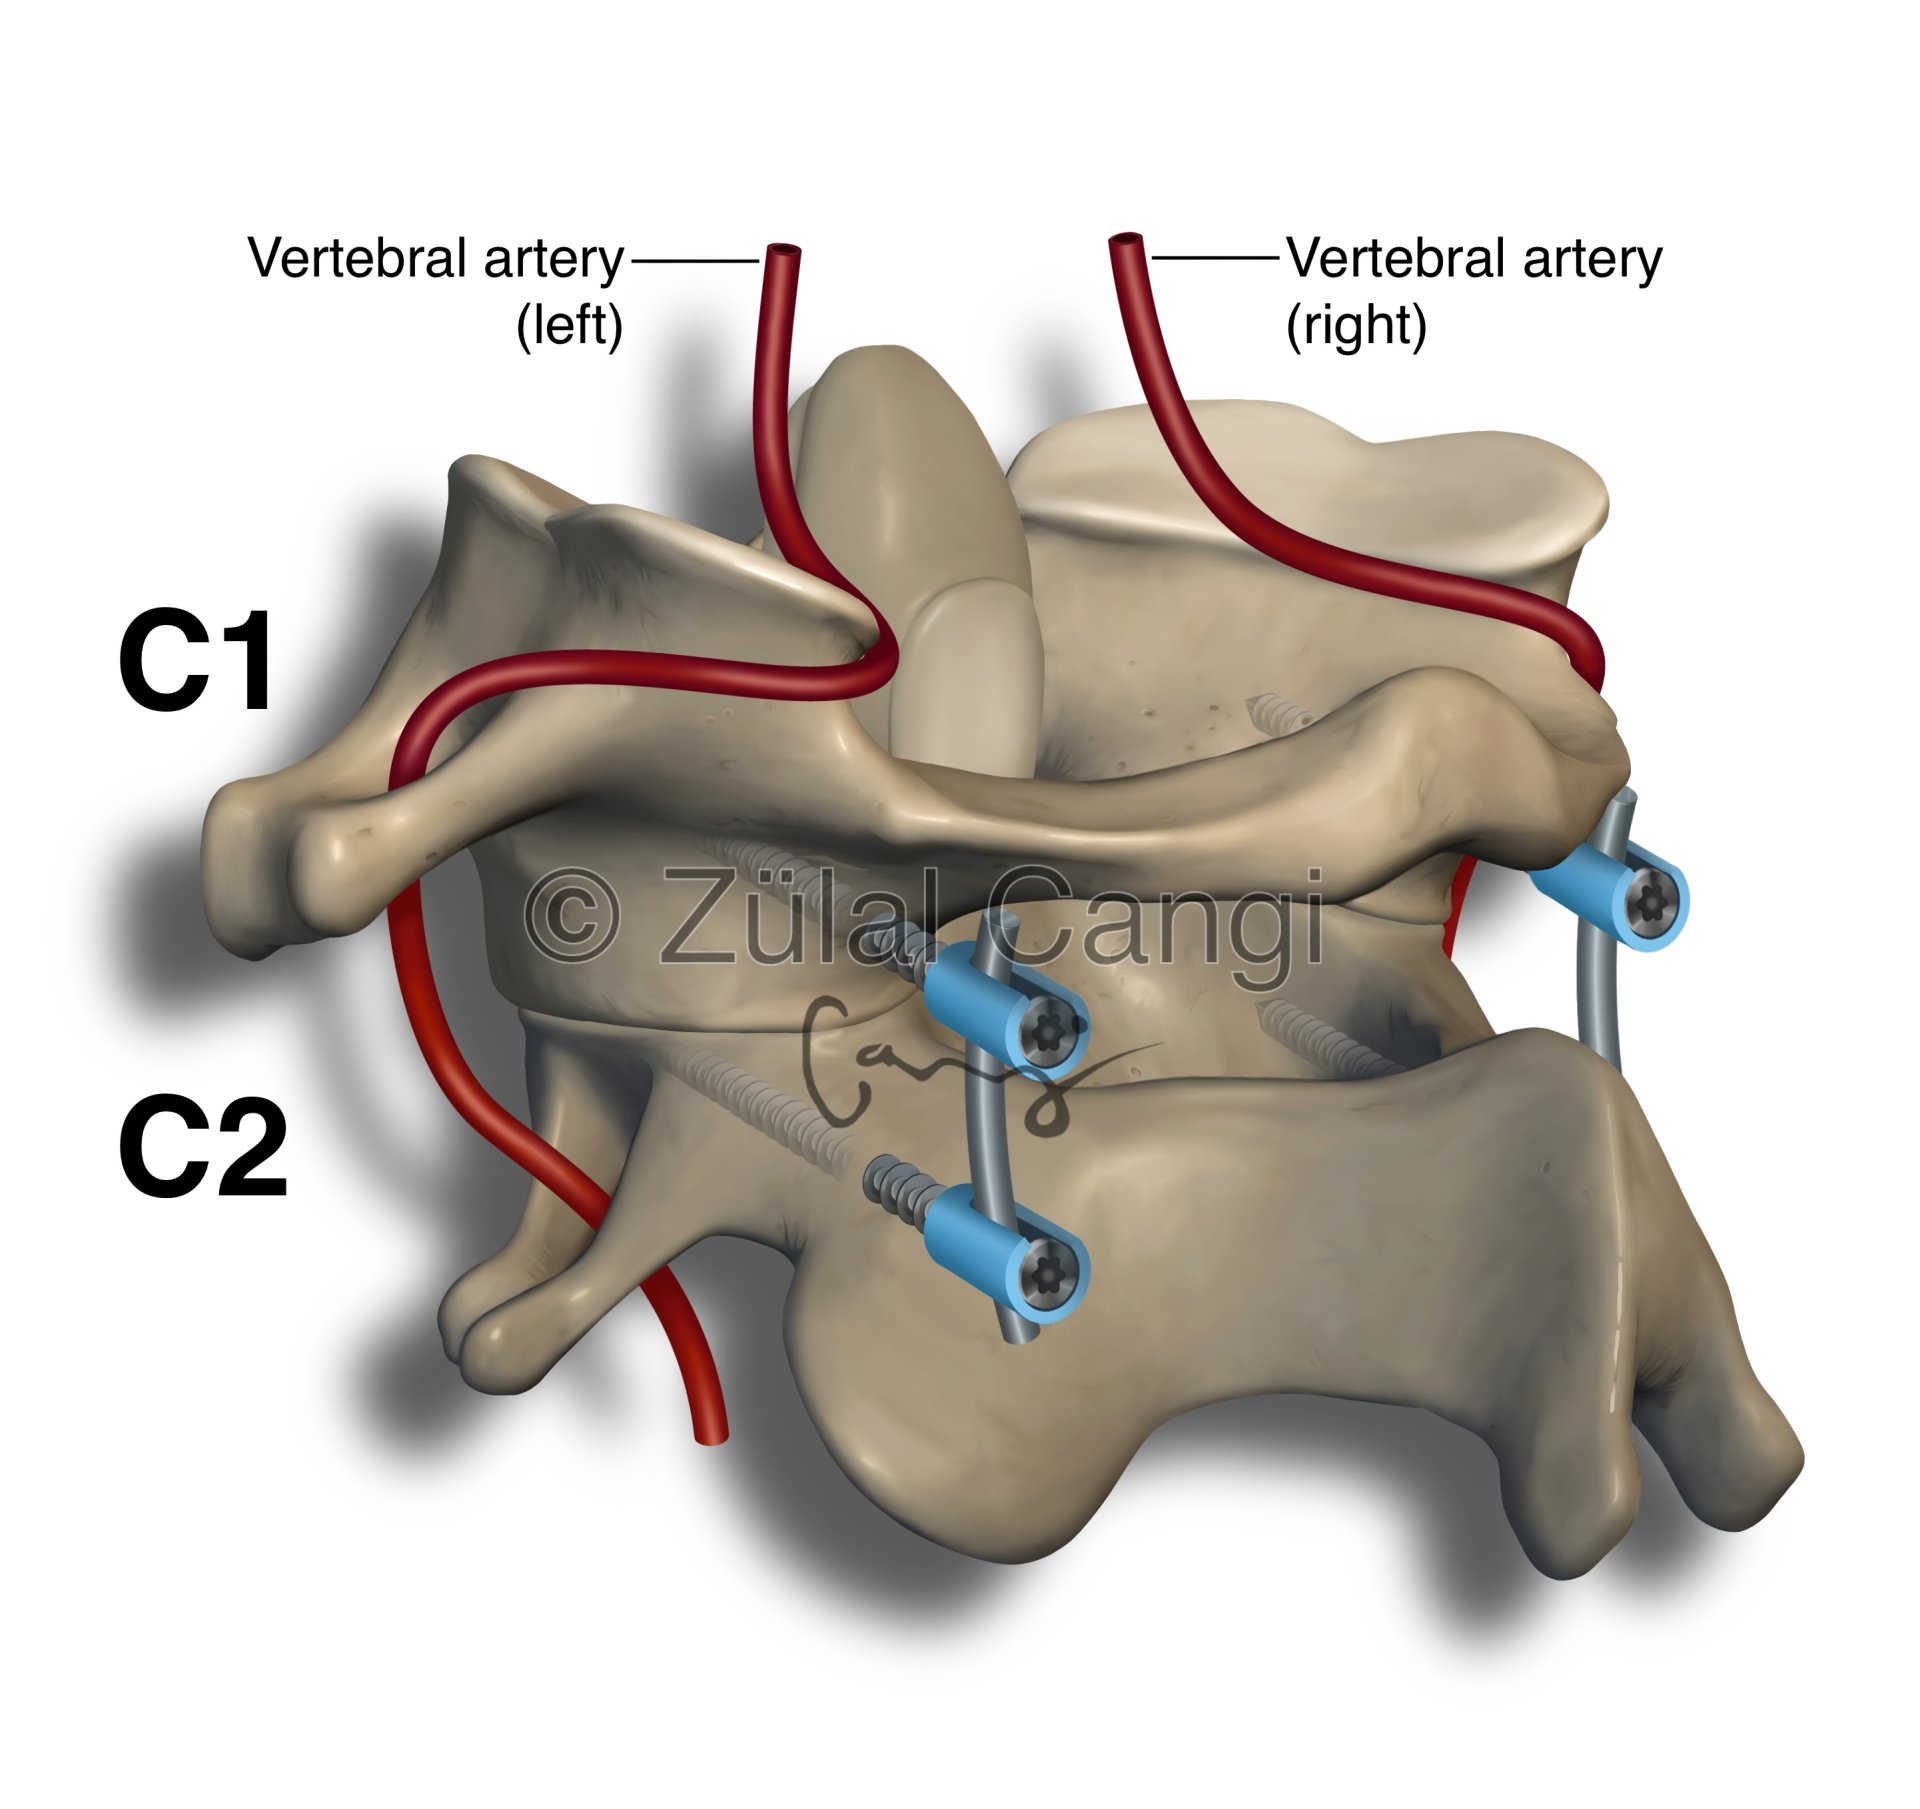

Sanatın estetiğini bilimin kesinliğiyle bir araya getiren Zülal Cangi, medikal ve bilimsel illüstrasyon alanındaki çalışmalarıyla akademik yayınlar, eğitim materyalleri ve çeşitli bilimsel platformlar için görsel içerikler üretmektedir. Amacı, bilimsel bilgiyi yalnızca doğru biçimde aktarmakla kalmayıp, aynı zamanda öğretici ve estetik bir dille görünür kılmaktır.

PORTFÖY